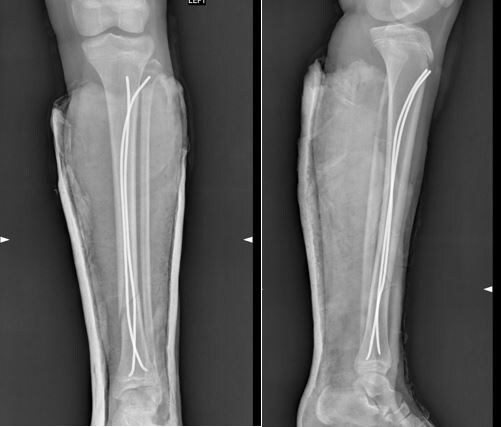

Переломы костей голени - частая травма у детей. Применение современных малотравматичных методов остеосинтеза позволяет детям восстановиться гораздо быстрее и комфортнее, чем раньше.

Фиксация титановыми эластичными стержнями - это современный метод лечения, при котором через небольшие хирургические доступы внутрь кости вводят тонкие гибкие стержни из титана. Благодаря конструкции и правильной технике имплантации они удерживают отломки в правильном положении, пока кость срастается.

🔹малотравматичная операция (для установки TENов достаточно двух небольших хирургических доступов по несколько сантиметров);

🔹надёжная фиксация;

🔹нет необходимости в длительной гипсовой фиксации;

🔹ребёнок раньше начинает ходить и восстанавливаться;

🔹как только спадает отёк после операции – гипсовая повязка снимается и ребенок начинает наступать на ногу.